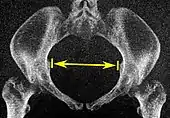

| Interspinous distance | ![]() |

![]() Axial plane |

The line between the closest bone points of the ischial spines | 9.5 to 11.5 cm.[6] | |